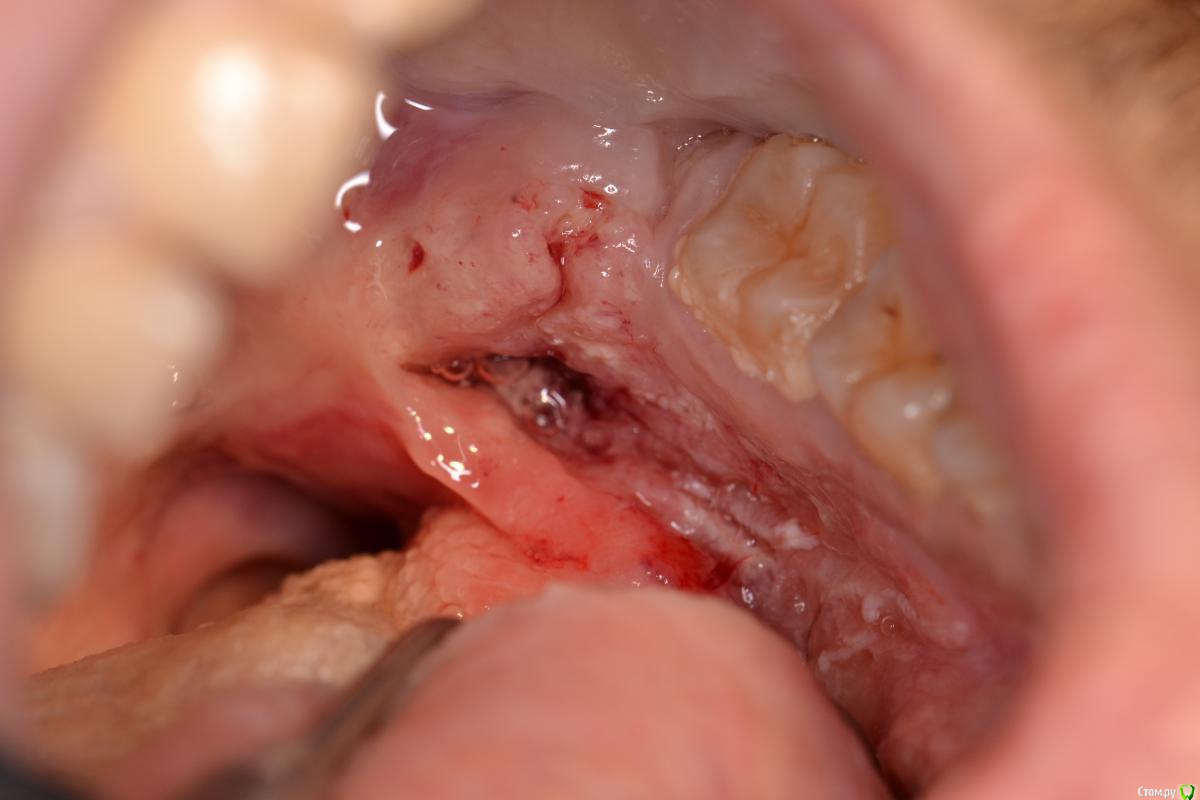

TIGER Опубликовано 22 декабря, 2016 Поделиться Опубликовано 22 декабря, 2016 Пациент 30 лет...жалобы на боли,затрудненное открываение рта...объективно на фото,при осмотре был удалён секвестр...заподозрил плохое...отправил в стационар...сегодня ответ....Cr...будьте бдительны при диагностике.... Ссылка на комментарий

Тимур86 Опубликовано 27 декабря, 2016 Поделиться Опубликовано 27 декабря, 2016 Вставлю свои 5 копеек.Остеосаркома.Изменения на слизистой пациент начал отмечать после травматичного удаления 46-го примерно год назад.http://s018.radikal.ru/i526/1612/83/be427148e9e5.jpg http://s018.radikal.ru/i522/1612/09/7624b427a4fb.jpg http://s019.radikal.ru/i602/1612/86/f393c6dc1767.jpg http://s019.radikal.ru/i643/1612/3f/aa9028208553.jpg http://s008.radikal.ru/i305/1612/84/ad71b30f876d.jpg Ссылка на комментарий